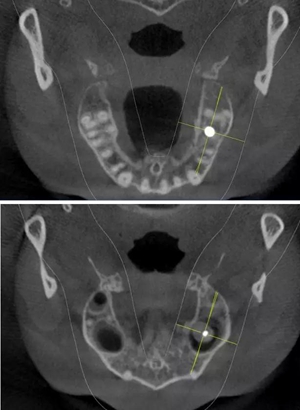

術(shù)前CBCT檢查

骨高度不足,內(nèi)提升的適應(yīng)癥??梢姼]膜致密,厚度均勻。骨高度不足,骨寬度尚可。

術(shù)后CBCT

提升時相關(guān)步驟可參考下面圖片

可見在完善的檢查和適當(dāng)?shù)墓ぞ哌x擇下可順利完成較復(fù)雜的上頜竇手術(shù)。